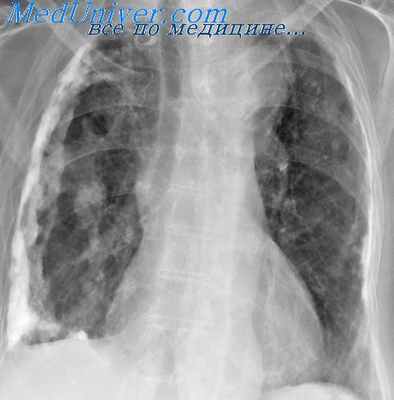

Как правило, исследование только в прямой проекции, не позволяет поставить диагноз. Типичная скиалогическая картина междолевого осумкованного плеврита имеет отображение на боковой рентгенограмме.

В нижеприведенной таблице, отображена скиалогическая картина, наблюдаемая при междолевом осумкованной плеврите.

Снижение прозрачности в прямой проекции

Нечетко очерченная тень округлой или овальной формы по типу фокусной, однородной структуры с нечёткими, размытыми контурами.

Снижение прозрачности в боковой проекции

Затемнение топографически соответствует главной междолевой щели и малой междолевой щели (справа).

Вытянутая, веретенообразная, линзообразная постепенно сужающаяся в виде линейных теней, что отображает уплотненную междолевую плевру. Треугольная форма - при примыкании к диафрагме.

Междолевой П. проявляется тенью в форме двояковыпуклой линзы. В прямой проекции хорошо виден выпот, осумкованный в горизонтальной щели правого легкою: нижний контур тени выпота обычно более выпуклый, чем верхний. Междолевые выпоты значительно лучше видны в боковой проекции (рис. 6). Нижний полюс линзообразной тени междолевого выпота обычно более широк, чем верхний. В прямой проекции междолевой выпот, особенно расположенный в горизонтальной щели, может иметь округлую форму и имитировать внутрилегочные образования, в частности периферический рак. Но в отличие от рака при междолевом выпоте определяются такие симптомы, как линейная полоска утолщенной плевры, отходящая от краев тени выпота, утолщение плевры в соседних отделах, линзообразная форма выпота.